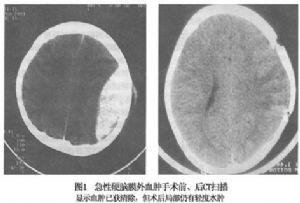

5.出院後應於1~3個月內進行隨訪調查,以瞭解手術效果和可能存在的顱內併發症(圖1)。

CT表現爲呈雙凸鏡形密度增高影,邊界銳利,骨窗位可顯示血腫部位顱骨骨折。同側腦室系統受壓,中線結構向對側移位(圖2,3)。